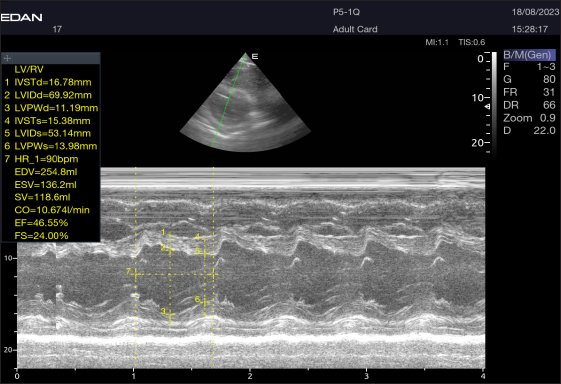

By positioning the probe perpendicularly in the fourth intercostal space or longitudinally in the fifth space with a little clockwise rotation, the interventricular septum, ventricles, and atria could be observed in the caudal long-axis four-chamber view (Fig. 1). From this vantage point, all camels could be seen to have a left ventricle, mitral valve, interventricular septum, right ventricle, and tricuspid valve. Figure 2 shows that in the short-axis image of the cardiac ventricles obtained with a little clockwise rotation at the 4th ICS, only the right ventricle, interventricular septum, and left ventricle were visible. Here, the dimensions of all camel heart were measured in M mode. The right parasternal two-dimensional short-axis pictures of the heart’s base in the first frame were used to determine the LA/Ao ratio, by applying 2D and M mode (Figs. 3 and 4). Despite some difficulties, we successfully acquired a pulmonary image by attempting to acquire the right ventricular outflow tract for the right short axis at the level of the great vessels.

Fig. 2. Short-axis plane M mode (Mushroom shape) of a 16-year-old racing girl camel at level papillary muscle showing left ventricular dimensions (systole and diastole). IVSTd=intraventricular septal wall thickness end-diastolic, LVPWd=left ventricle posterior wall thickness end-diastolic, LVIDd=left ventricular internal dimension, LVIDs=left ventricular internal dimension end-systolic, LVPWs=left ventricle posterior wall thickness, IVSTs=intraventricular septal wall thickness end-systolic, HR=heart rate, EDV=end-diastolic volume, ESV=end-systolic volume, CO=cardiac output, EV=ejection fraction, SV=stroke volume, FS=fractional shortening.